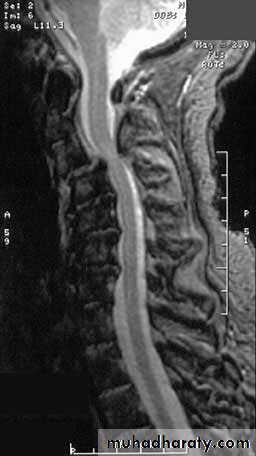

MR imaging